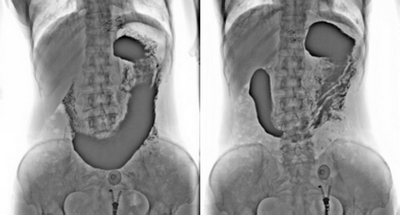

3. 數字化胃腸:

★消除普通數字胃腸機視野小的缺陷,直接獲得大視野全數字化圖像 (17x17) 。

★更加方便胃腸、食管、上消化道、全消化道等造影功能!

★通過動態攝影觀察組織器官的功能運行情況,并輕松進行點片拍攝。

★各種普通及特殊造影,如口服膽囊造影、靜脈膽道造影、T管造影、逆行胰膽管造影(ERCP)、靜脈腎盂造影(IVP)、子宮輸卵管造影、脊髓造影等。